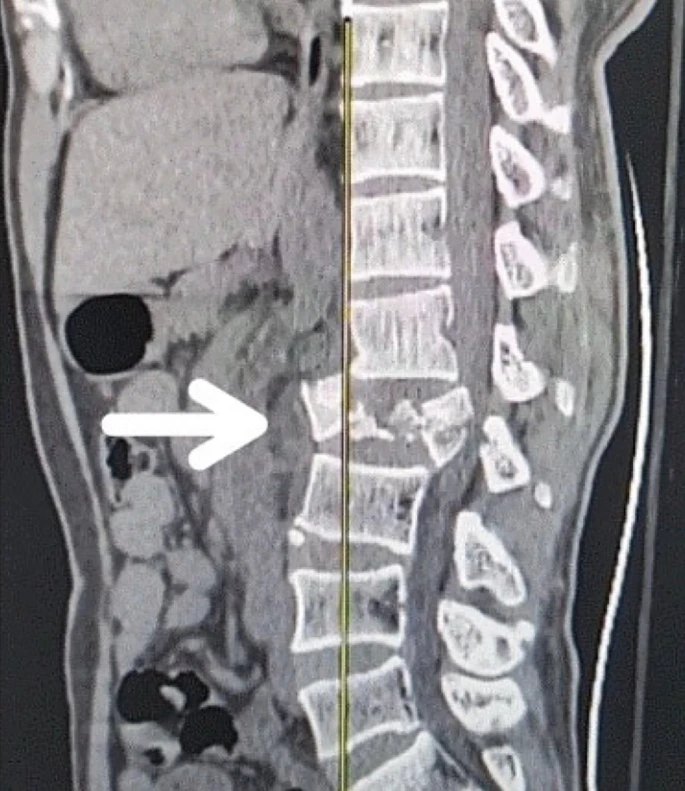

創傷性脊髓損傷是由于脊柱受到突然的強力撞擊,導致椎骨骨折、脫臼、擠壓或壓縮(圖1)。主要原因包括機動車事故,其中汽車和摩托車碰撞占每年新增脊髓損傷病例的近一半。跌倒,尤其是65歲及以上人群的跌倒,是造成脊髓損傷的重要原因,約占60%。體育活動,例如沖擊性運動和淺水潛水,約占此類損傷的10%。

慢性期開始于損傷后約3-6個月,并持續患者的余生,典型特征是囊腫形成和嚴重的神經膠質瘢痕(圖2)。